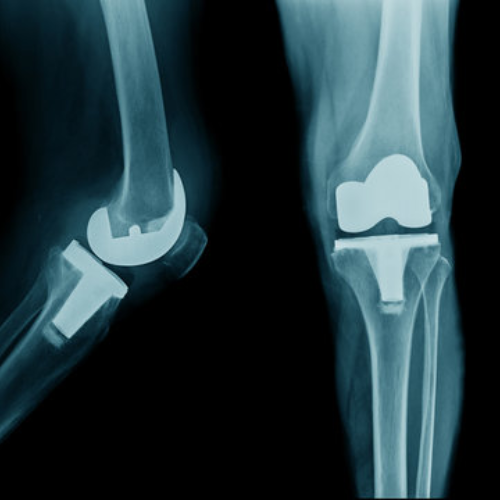

Arthroplasty is a surgical procedure that involves replacing a damaged joint with an artificial implant to restore mobility and eliminate pain. It is most commonly performed on weight-bearing joints like the knee, hip, and shoulder, especially when conservative treatments fail to provide relief.

• Total Knee Replacement (TKR)

• Partial Knee Replacement